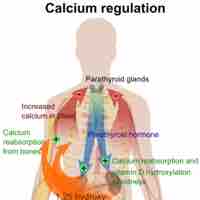

Bone remodeling or bone turnover is the process of resorption followed by replacement of bone and occurs throughout a person's life.